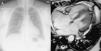

La resonancia magnética cardiaca aporta abundante información morfológica y funcional al estudio de las cardiopatías congénitas. Entre los datos funcionales se encuentran el gasto pulmonar y el gasto sistémico; el cociente entre ambos es el cociente Qp/Qs. Después del nacimiento, en condiciones normales el gasto pulmonar y el sistémico son prácticamente iguales, y el cociente Qp/Qs=1. En los pacientes con cortocircuitos entre la circulación sistémica y la pulmonar este cociente se altera. Dependiendo de la localización del cortocircuito (intra o extracardiaco), y de las alteraciones estructurales o posquirúrgicas asociadas, la interpretación de los hallazgos es diferente. Revisamos el concepto de Qp/Qs, los métodos para calcularlo con especial énfasis en la RM, y el significado de los resultados obtenidos, haciendo hincapié en la relevancia de estos datos dependiendo de la patología de base y los procedimientos terapéuticos que se hayan realizado al paciente.

Cardiac magnetic resonance imaging (cMRI) provides abundant morphological and functional information in the study of congenital heart disease. The functional information includes pulmonary output and systemic output; the ratio between these two (Qp/Qs) is the shunt fraction. After birth, in normal conditions the pulmonary output is practically identical to the systemic output, so Qp/Qs=1. In patients with «shunts» between the systemic and pulmonary circulations, the ratio changes, and the interpretation of these findings varies in function of the location of the shunt (intracardiac or extracardiac) and of the associated structural or postsurgical changes. We review the concept of Qp/Qs; the methods to calculate it, with special emphasis on cMRI; and the meaning of the results obtained. We place special emphasis on the relevance of these findings depending on the underlying disease and the treatment the patient has undergone.